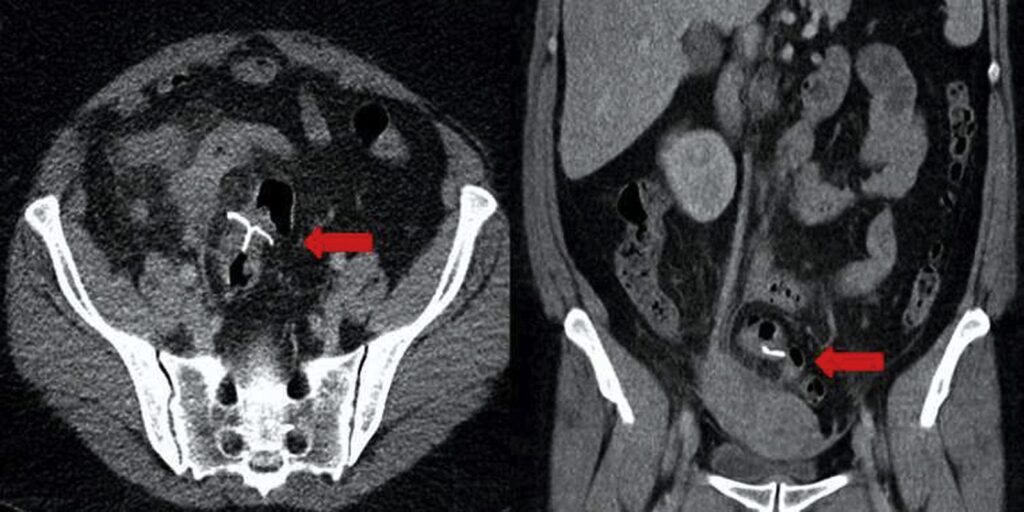

- Ecografía: En algunos casos, se puede realizar una ecografía para observar los órganos pélvicos y descartar otras afecciones.

El tratamiento para la EIP se basa en el uso de antibióticos para eliminar las bacterias causantes de la infección. Es vital comenzar el tratamiento lo antes posible para evitar complicaciones a largo plazo. Una pregunta frecuente es si se debe retirar el DIU. Si los síntomas mejoran rápidamente con los antibióticos (generalmente en las primeras 48-72 horas), a menudo no es necesario retirar el dispositivo.